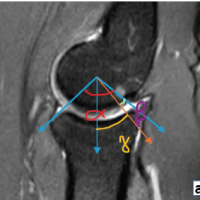

Magnetic resonance imaging (MRI) of the dorsal spine demonstrated altered marrow signal and heterogeneous post-contrast enhancement involving the D1, D2, and D10 vertebral bodies. An enhancing soft-tissue mass extended into both anterior and posterior epidural spaces at the D1–D2 level, causing severe spinal canal narrowing with cord compression and myelopathic signal changes. Extension was noted along the bilateral neural foramina and posterior elements of D1–D3 (Fig. 2). Additional short tau inversion recovery-hyperintense foci were seen in D11, D12, L1, L3, and L5 vertebrae, several of which showed mild enhancement, raising concern for multifocal metastatic deposits.

Figure 2: Pre-operative magnetic resonance imaging of the dorsal spine showing altered marrow signal and enhancing lesion involving the D1–D2 vertebral bodies with an epidural soft-tissue component causing severe spinal canal narrowing and cord compression with associated myelopathic signal changes. Additional axial and sagittal sequences demonstrate the extent of epidural involvement and compression.